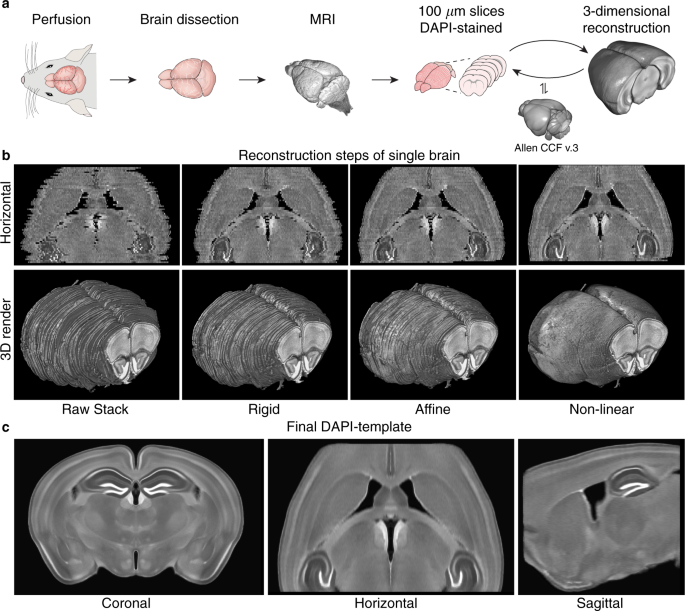

In this study, we sought to allow for template-based segmentation of 2-dimensional mouse brain slices acquired with fluorescence microscopy. Typically, a stain called DAPI is used to show the brain structures, and up to three additional channels are used for measuring the molecule(s) of interest. So, we needed to construct a population-based template of the mouse brain from slices stained with DAPI.

We collected consecutive coronal slices from 12 mice (C57BL/6) covering the majority of the cerebrum and DAPI-stained them. With the help of Allen Mouse Brain Common Coordinate Framework (CCFv3) we were able to reconstruct all 12 brains. This was done by iteratively stacking the 2-dimensional slices into 3-dimensional volumes, registering, and slicing. With the reconstructed brains, we could perform the template creation in 3-dimensional space. Using this new template in combination with the CCFv3 we started over with the reconstruction and template creation resulting in the final well-defined DAPI template (shown in the beginning of the post).

We were thrilled with how well the reconstruction process worked and happy to see a well-defined and smooth template. New coronal slices were easily registered to the template, so we wrote a small python program for automatic template-based segmentation (see the full paper for examples). To encourage the scientific community to utilize and improve the template, we have made all the data available in a well-structured and ordered fashion here: https://doi.org/10.12751/g-node.16wrxa